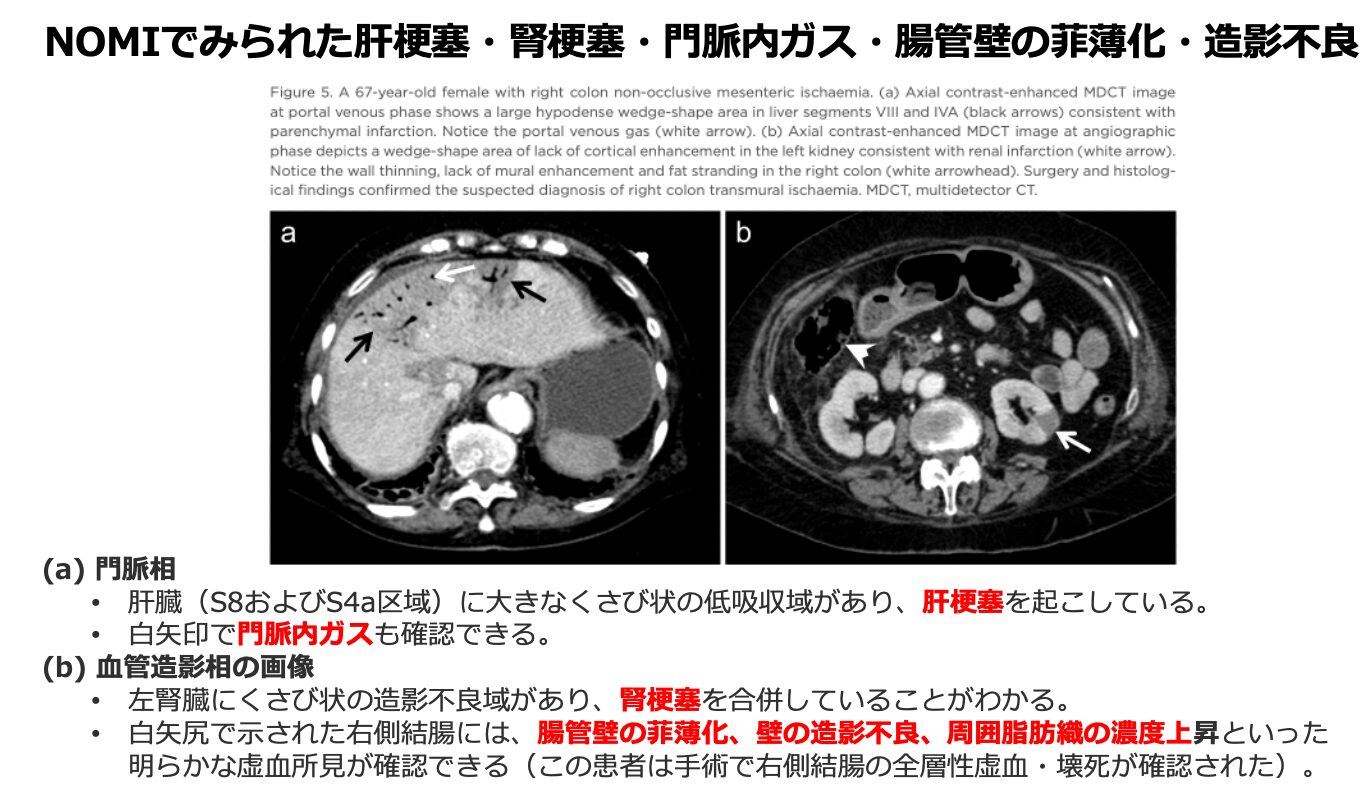

- 門脈内ガス: 22%(23例)に認められます。腸管気腫症のガスが腸間膜静脈から門脈系へと進行したことを示します。

【実質臓器の梗塞】 NOMIの鑑別において、他臓器の梗塞所見を伴うことは特異度の高い徴候となります。

- 肝梗塞: 約16%(17例)

- 腎梗塞: 約12%(13例) ※稀に気腫性胆嚢炎(約1%)を合併することもあります。

3. 周囲の変化に注目する(血管内ガス・脂肪織の吸収値上昇)

- 腸管壊死を示唆するさらに重篤なサインとして、腸間膜静脈内や門脈内のガスがないかを探します。また、周囲の腸間膜脂肪織の吸収値が上昇していないかにも注目します。

- 他臓器の梗塞の確認: 腸管だけでなく、脾臓、肝臓、腎臓などの実質臓器に梗塞(造影不良域)を伴っていないか確認することも、NOMIを疑う上で非常に有用なサインとなります。